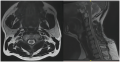

【质子案例分享】儿童鞍区生殖细胞瘤质子治疗11岁女孩,3年前出现多饮多尿,体重逐渐增加,2年前双眼视力进行性下降,当地医院就诊后未明确诊断。近1年患者体重明显增加约20斤,视力下降较前加重,行颅脑MR示:鞍区占位。手术穿刺病理示:鞍区生殖细胞来源肿瘤,结合形态及酶标,符合生殖细胞瘤。分子病理结果:EBER(-),免疫组化:AE1/AE3(-), ALK(-), CD1a(-), CD30(-), EMA(-), GFAP(-),Ki-67(部分+),Langerin(-), LCA(-), NEU-N(-), OLig-2(-), S-100(-), Syn(-), Vimentin(-), CD117(+), GPC-3(-),OCT3/4(+),PLAP(+),SALL4(+)。术后双